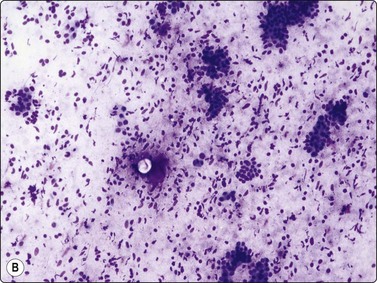

image image

Fig. 7.1 Radiation-induced atypia

(A) The epithelial cells in this irregular cluster show considerable nuclear enlargement, pleomorphism and hyperchromasia, but also some degenerative changes such as loss of nuclear structure (MGG, HP); (B) Corresponding tissue section (H&E, IP).